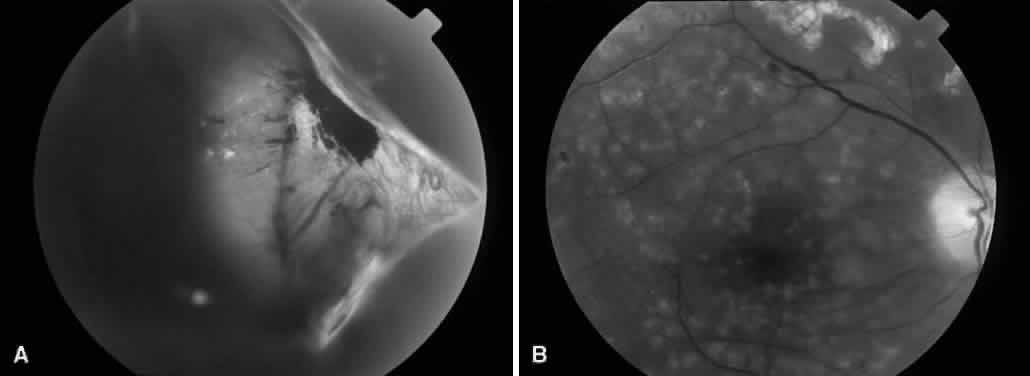

MACULAR TRACTION RETINAL DETACHMENT

Fig. 4. An example of an eye with proliferative diabetic retinopathy and traction retinal detachment involving the macula.

Vitreous traction and contraction of proliferative tissue can produce retinal tears, leading to combined traction-rhegmatogenous detachments. Unlike purely tractional detachments, extramacular rhegmatogenous detachments frequently progress to involve the macula, leading to rapid and severe visual loss. Thus, surgical repair is indicated in combined detachments, whether or not the macula is involved. Often, the retinal breaks are located posterior to the equator, adjacent to areas of fibrovascular proliferation that are under severe vitreoretinal traction. Therefore, this condition is difficult to treat by conventional scleral buckling methods, whereas vitrectomy (with or without scleral buckling) is effective in treating this condition (Fig. 5). Intraocular long-acting gas tamponade is required to treat these detachments. Combined traction-rhegmatogenous detachments have a lower success rate than pure tractional detachments or nonclearing vitreous hemorrhage. In an analysis of 172 eyes that underwent vitrectomy for combined traction-rhegmatogenous diabetic retinal detachment, 48% had an improved visual acuity on final examination.21 A final visual acuity of 20/100 or better was achieved in only 25% of eyes, and a final visual acuity of 5/200 was achieved in 56%. Visual loss progressed to no light perception in 23% (compared with 19% for macular traction detachment and 6% for nonclearing vitreous hemorrhage). Preoperative factors associated with a favorable visual prognosis included visual acuity of 5/200 or better, absence of iris neovascularization, and absence of retinal detachment involving the macula. The only intraoperative factor found to be associated with a favorable visual prognosis was the absence of iatrogenic retinal breaks.

Fig. 5. A. Preoperative fundus photograph of an eye with combined traction-rhegmatogenous retinal detachment from severe proliferative diabetic retinopathy. B. Postoperative fundus photograph of the same eye after vitrectomy, membrane dissection (using delamination technique), and endolaser photocoagulation.